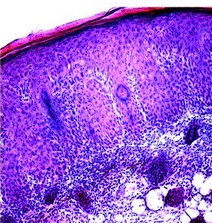

Ø pour traiter le psoriasis : « dans le psoriasis », souligne le Dr Marinkovich, auteur principal, « le ciblage d'une protéine dans la peau, plutôt que du système immunitaire, pourrait être une option avantageuse pour de nombreux patients et pour les cliniciens ». Ainsi, les chercheurs montrent que Rac1 est fortement activé dans les biopsies de la peau psoriasique de 20 patients atteints. De même, lorsqu'ils activent artificiellement Rac1 dans la peau de souris de laboratoire, les animaux présentent alors des symptômes similaires à ceux des patients humains (Visuels du haut).

Il apparaît possible de bloquer/réguler l'activité de la protéine : le blocage de l'activité de Rac1 dans des biopsies de peau humaine psoriasique greffées sur le dos des souris, inverse l'hyperplasie de la peau (cf vignette) et réduit le recrutement de molécules immunitaires appelées cytokines. Cibler l'activation de Rac1 dans la peau peut donc être un moyen de traiter le psoriasis, sans toucher au système immunitaire. La prochaine étape consistera à développer des médicaments topiques, sous forme de gel ou de pommade, capables de réguler à la baisse ou à la hausse l'activation de Rac1 anormale dans le psoriasis mais bienvenue dans la cicatrisation.